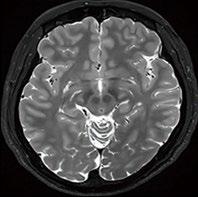

Fig 1: Next generation MRI is being used to gather data on brain tissue volumes Dr. Steve McNally

From this season at Manchester United Football Club, we have started to gather data by using MRI (see fig 1) to measure volumes of brain tissue in specific areas, to monitor for a decrease in volumes over time. If the volumes become unusual or deviate from the norms that we would expect, it may help us identify early changes of CTE that need closer monitoring. This is a new, long-term data gathering study in our cohort of players that has been facilitated with the new next generation MRI3 now in place at our medical centre.